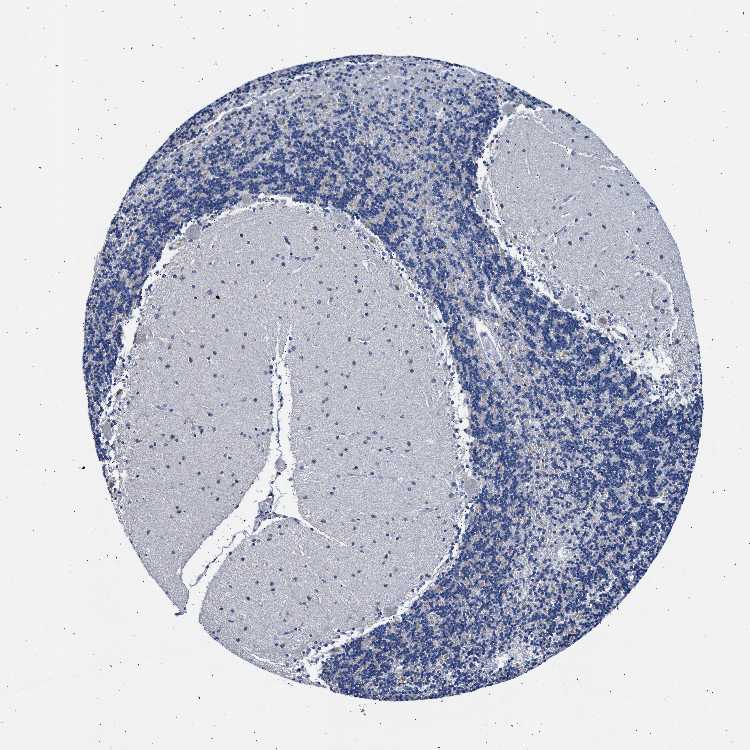

CEREBELLUM - Antibody stainingi

Antibody staining in the annotated cell types in the current human tissue is reported as not detected, low, medium, or high, based on conventional immunohistochemistry profiling in selected tissues. This score is based on the combination of the staining intensity and fraction of stained cells.

Each image is clickable and will lead to virtual microscopy that enables deeper exploration of all samples and also displays staining intensity scores, fraction scores and subcellular localization as well as patient and tissue information for each sample.

Antibody HPA018020

Purkinje cells Low

Cells in granular layer Not detected

Cells in molecular layer Not detected